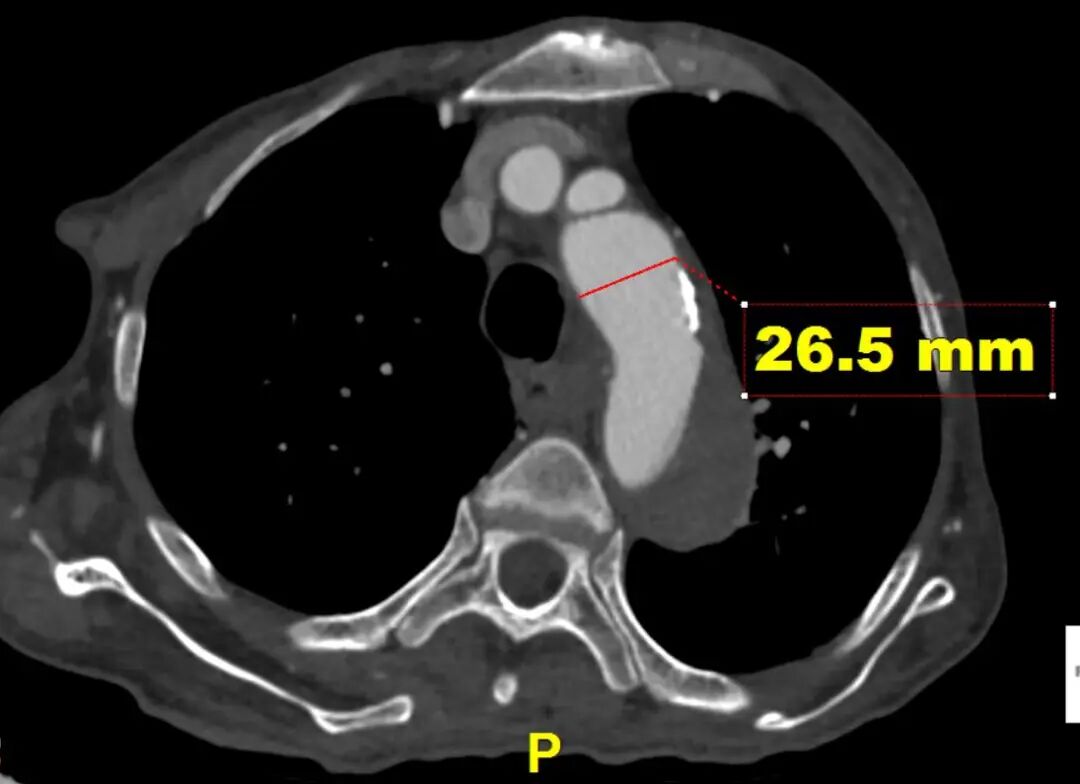

CTA提示患者主动脉弓型为Ⅲ型弓,左侧椎动脉为优势动脉,夹层累及至双侧髂外动脉,腹腔干动脉,肠系膜上动脉及左肾动脉为真腔供血,右肾动脉为真假腔供血,左侧胸腔少量积液。

远端真腔长轴直径

LSA后缘主动脉直径

对于此病例,近端未见明显破口,计划从左锁骨下动脉后缘锚定保证椎动脉血供,远端覆盖降主段主要破口,支架远端尽量处在相对直段的血管降低损伤血管风险。结合近端血管直径及远端真腔长轴直径计划近端:CADS支架 TGMR313120+远端CTAG TGU262610。